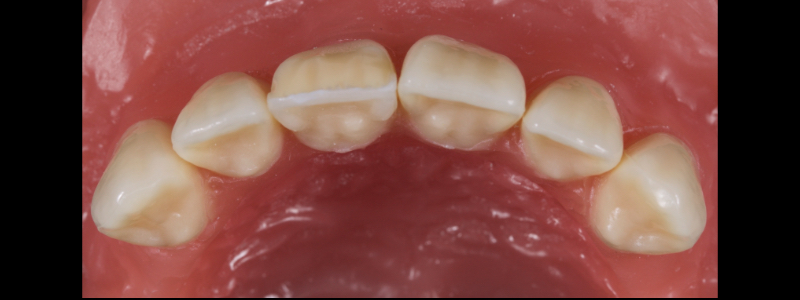

After deprogramming with a splint and occlusal equilibration, the anterior teeth were restored with direct composite resin using a minimal prep approach (Figs. 4 and 5). The occlusal scheme was idealized (Fig. 6).

In this case, a 23-year-old male presented with Ellis Class II fractures of both central incisors (Fig. 23). He had no interest in closing his diastema or restoring the peg laterals. A treatment plan was agreed upon to restore both central incisors with direct resin.